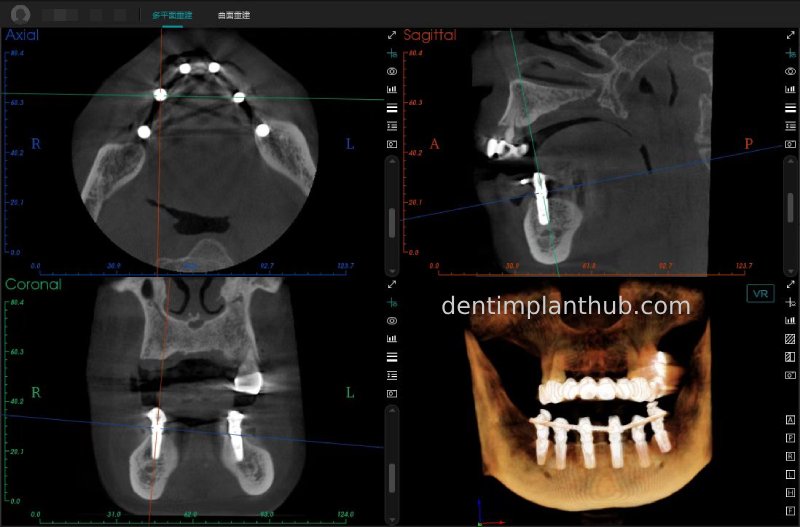

Maxillary condition as shown by CBCT on 13/5/24

16

14

12

22

24

26